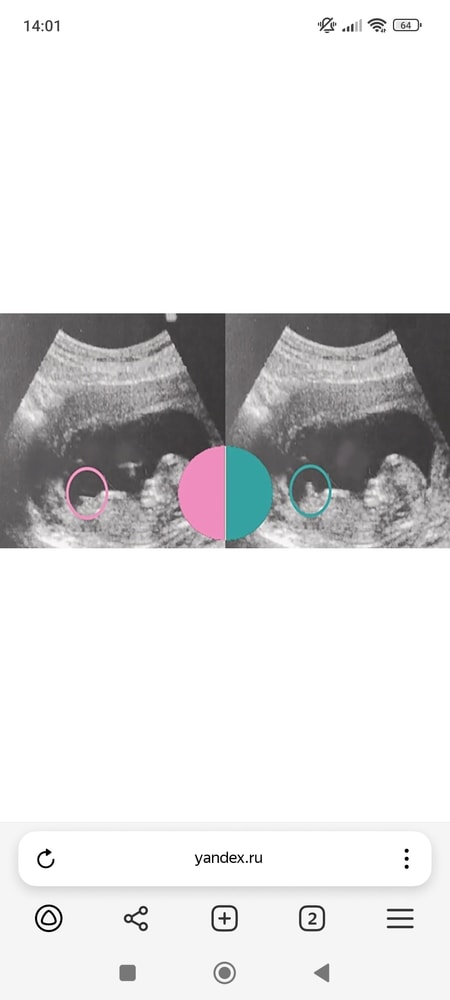

Изображение

Али, неужели так наглядно?!) спасибо))

Анна Романова, да,у меня в точности как на этом фото было))) на 12 неделе уже сказали пол, правда, в платной клинике